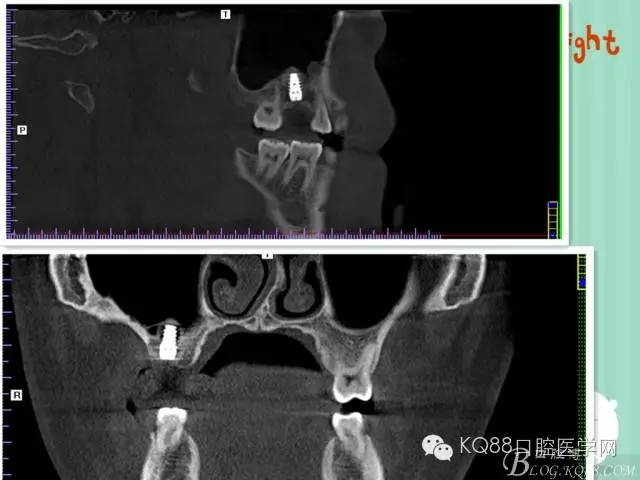

下面是拔牙前 CBCT

清晰可見根尖部陰影區(qū)域明顯。遠(yuǎn)中頰根

近中頰跟,同時可以看出離上頜竇比較近,且伴有骨缺損。

這個切面可以看到根裂。